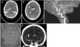

Subarachnoid cyst adjacent to calvarium

Macrocephaly